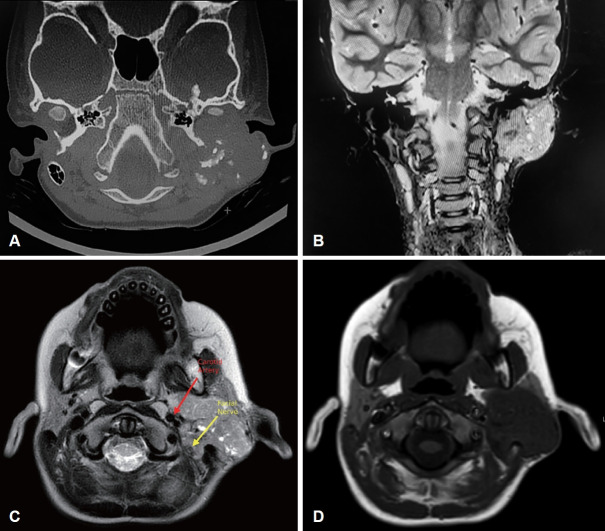

Myofibromatosis is a proliferative disorder characterized by the development of soft tissue neoplasms referred to as myofibromas that predominantly occur in infants and young children. These lesions have been described using varied terminologies since they were first reported in 1951. However, these neoplasms are histopathologically characterized by benign fibroblast and myofibroblast proliferation containing a biphasic presentation of spindle-shaped cells surrounding a central zone of less differentiated cells arranged in a hemangiopericytoma-like pattern in all cases. Usually, myofibromatosis occurs in children aged <2 years and is observed at birth in nearly 60% of cases. We report a rare case of myofibroma in an 8-year-old boy who presented with an approximately 6-month history of a left postauricular mass. Histopathological evaluation of the resected mass confirmed the diagnosis.